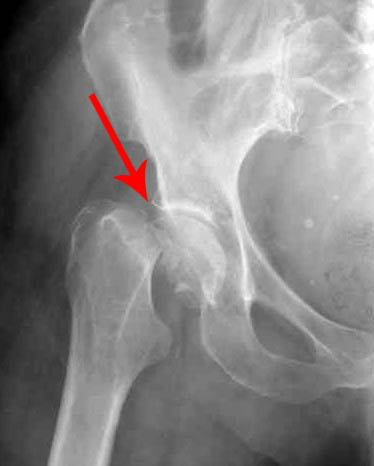

ดูภาพนี้แล้วจะเห็นได้ว่าในภาพไม่มีช่องว่างระหว่างกระดูก กระดูกถูกัน ทำให้เกิดอาการปวดอย่างรุนแรง และเมื่อเกิดอาการแบบนี้แล้วจะรักษาได้ยากมาก!